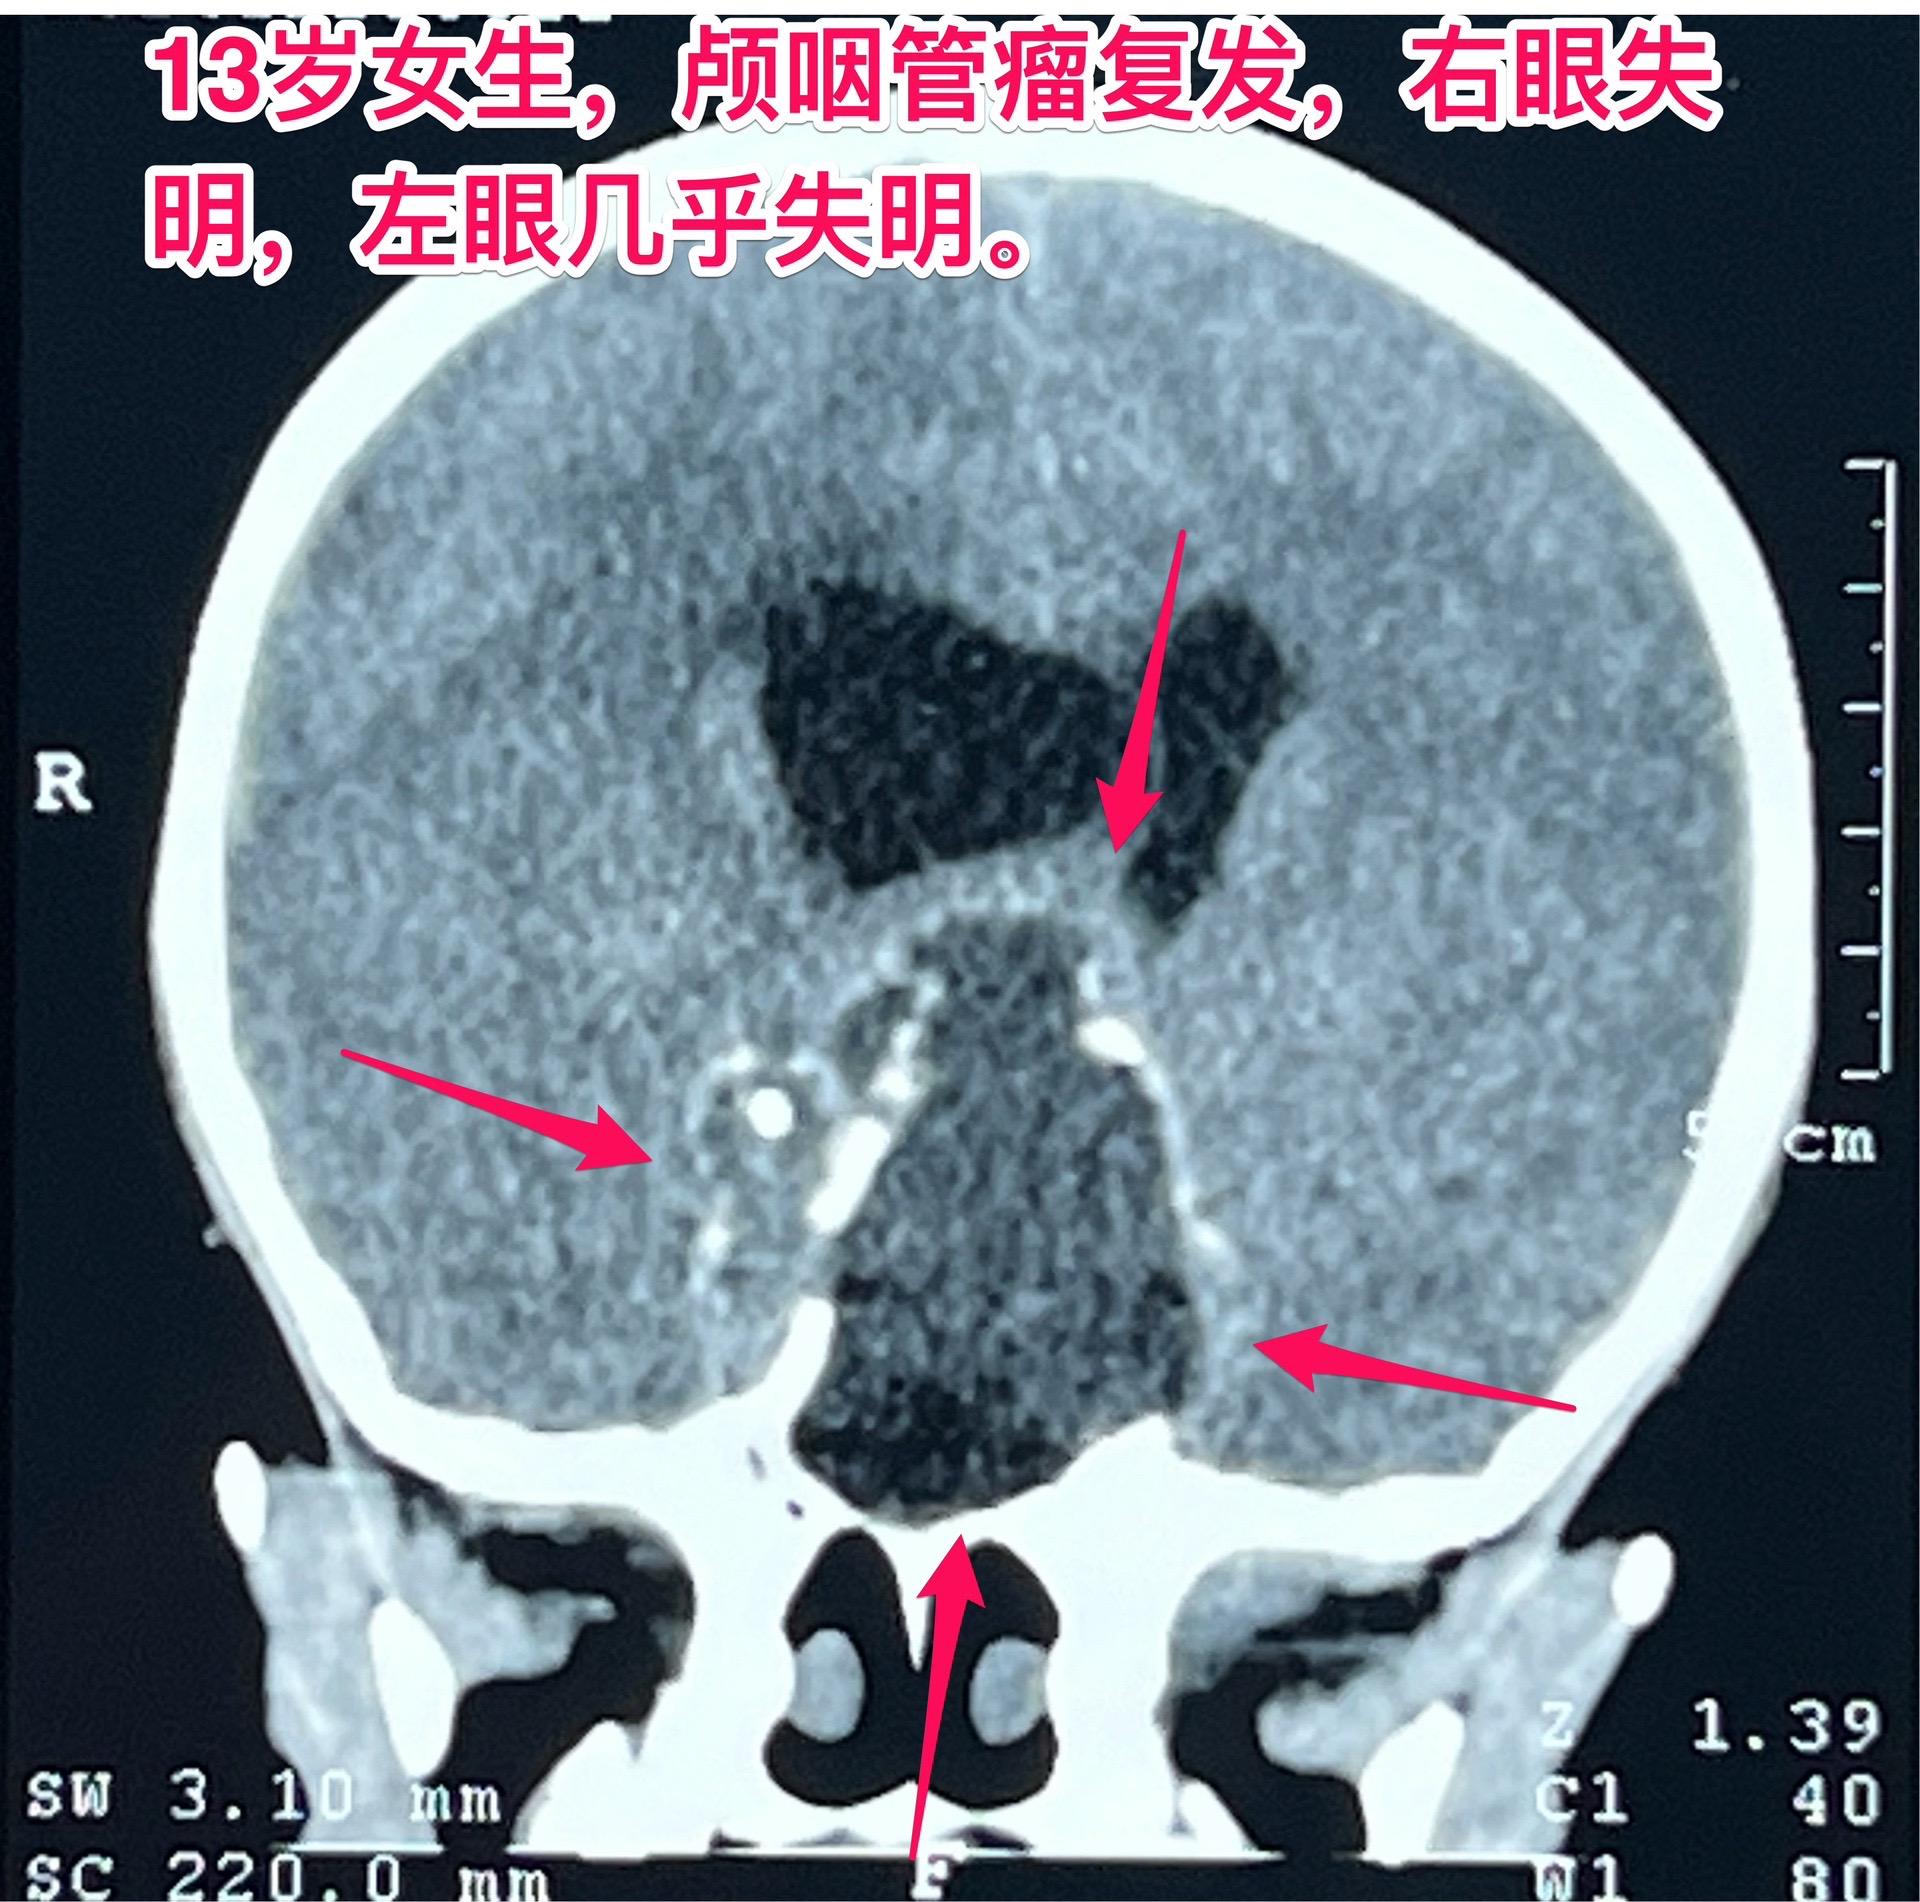

颅咽管瘤两次复发,右眼失明、左眼快失明了。13岁女孩子,因颅咽管瘤之前做过两次开颅手术。肿瘤又复发了,体积很大,垂体窝显著扩大,见图。 12月27日作了手术,将肿瘤完全切除。 这是第三次手术,手术前家长很担心左眼仅有的光感视力会不会变成全盲?会不会出现脑脊液鼻漏? 手术后患者很快就清醒了,左眼视力保住了,也没有脑脊液鼻漏出现。希望肿瘤不再复发。